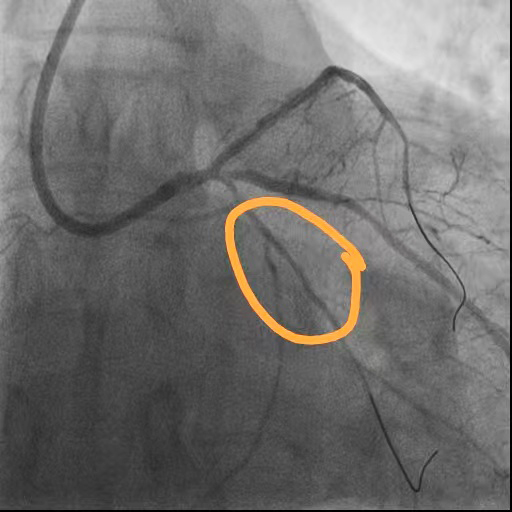

术后

回旋支狭窄解除

前降支闭塞段开通

右冠脉狭窄解除